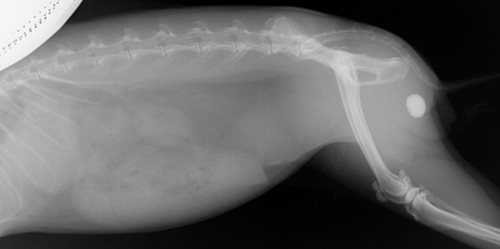

L’hématurie est confirmée par la réalisation d’une bandelette urinaire sur les urines émises. Une radiographie de la totalité de l’abdomen indique la présence d’un unique et volumineux calcul urinaire urétral (environ 2 cm). L’examen biochimique ne révèle pas d’anomalie.

Photo 1 : Radiographie mettant en évidence un calcul urétral.